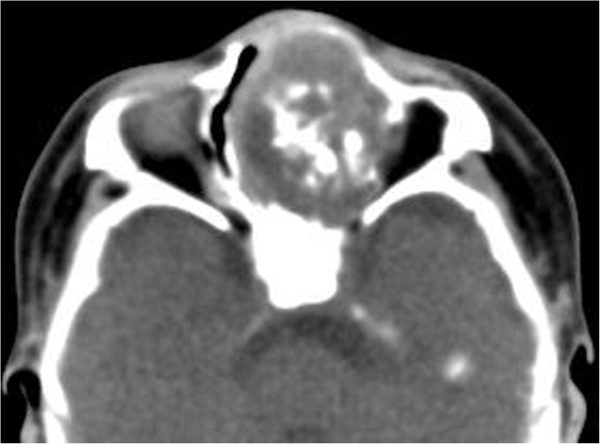

Figure 5.

MR Imaging of sinonasal cavity. (a) An axial T2-weighted MRI showed a well-defined, heterogeneous hyperintense mass containing multiple small round areas of higher signal intensity (arrow). (b) Axial contrast-enhanced fat-suppressed T1-weighted image demonstrated striking heterogeneous enhancement of the mass with multiple non-enhanced cystic components within the lesion (arrow).

A 6-week-old girl, born at full term by transvaginal delivery, presented with a 4-week history of left nasal watery rhinorrhea and obstruction. Physical examination revealed a purple polypoid mass in the left nasal cavity. All other findings of her medical and family history were unremarkable. Non-contrast CT scans revealed a 2.6 × 3.4 × 3.9 cm well-defined, expansile mass with amorphous calcification in the left nasal cavity (Figure 4). The mass caused pressure remodeling of the adjacent bones without evidence of destruction or invasion of the adjacent structures. MRI demonstrated that the signal intensity of the mass was heterogeneous on T1- and T2-weighted images. The T2-weighted images further showed multiple round areas of high signal intensity within the lesion. The majority of the mass showed a strongly heterogeneous enhancement and the multiple round areas of high signal intensity on T2-weighted images were demonstrated as non-enhancing cystic components after administration of contrast medium (Figure 5). Total resection of the mass was performed in this patient. Histopathologically, the mass was composed of multiple irregular cartilage islands in mesenchymal elements such as spindle cells in a myxoid stroma. The patient is currently doing well postoperatively, without evidence of residue or recurrence according to a 10-month follow-up CT scan.